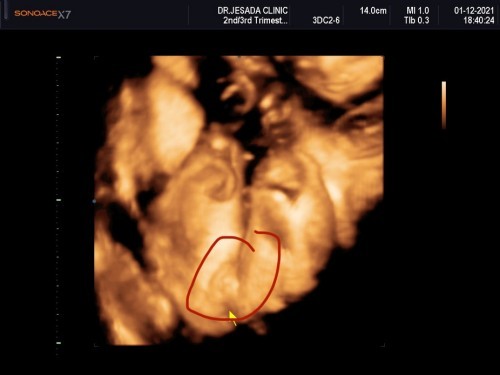

แบบนี้คือผู้หญิงหรือชายคะไม่ค่อยแน่ใจเท่าไหร่

หมอบอกน้องเป็นผู้หญิงแต่ก็ไม่ค่อยแน่ใจเท่าไหร่

ผู้หญิงหละค่ะ ถ้าผู้ชายมีตุ่มจู๋เห็นชัดเจน อันนี้เรียบๆ

คิดว่าหญิงนะคะ เพราะบ้านนี้ได้ผู้ชายโด๋ชัดแจ่วมาเลยค่ะ